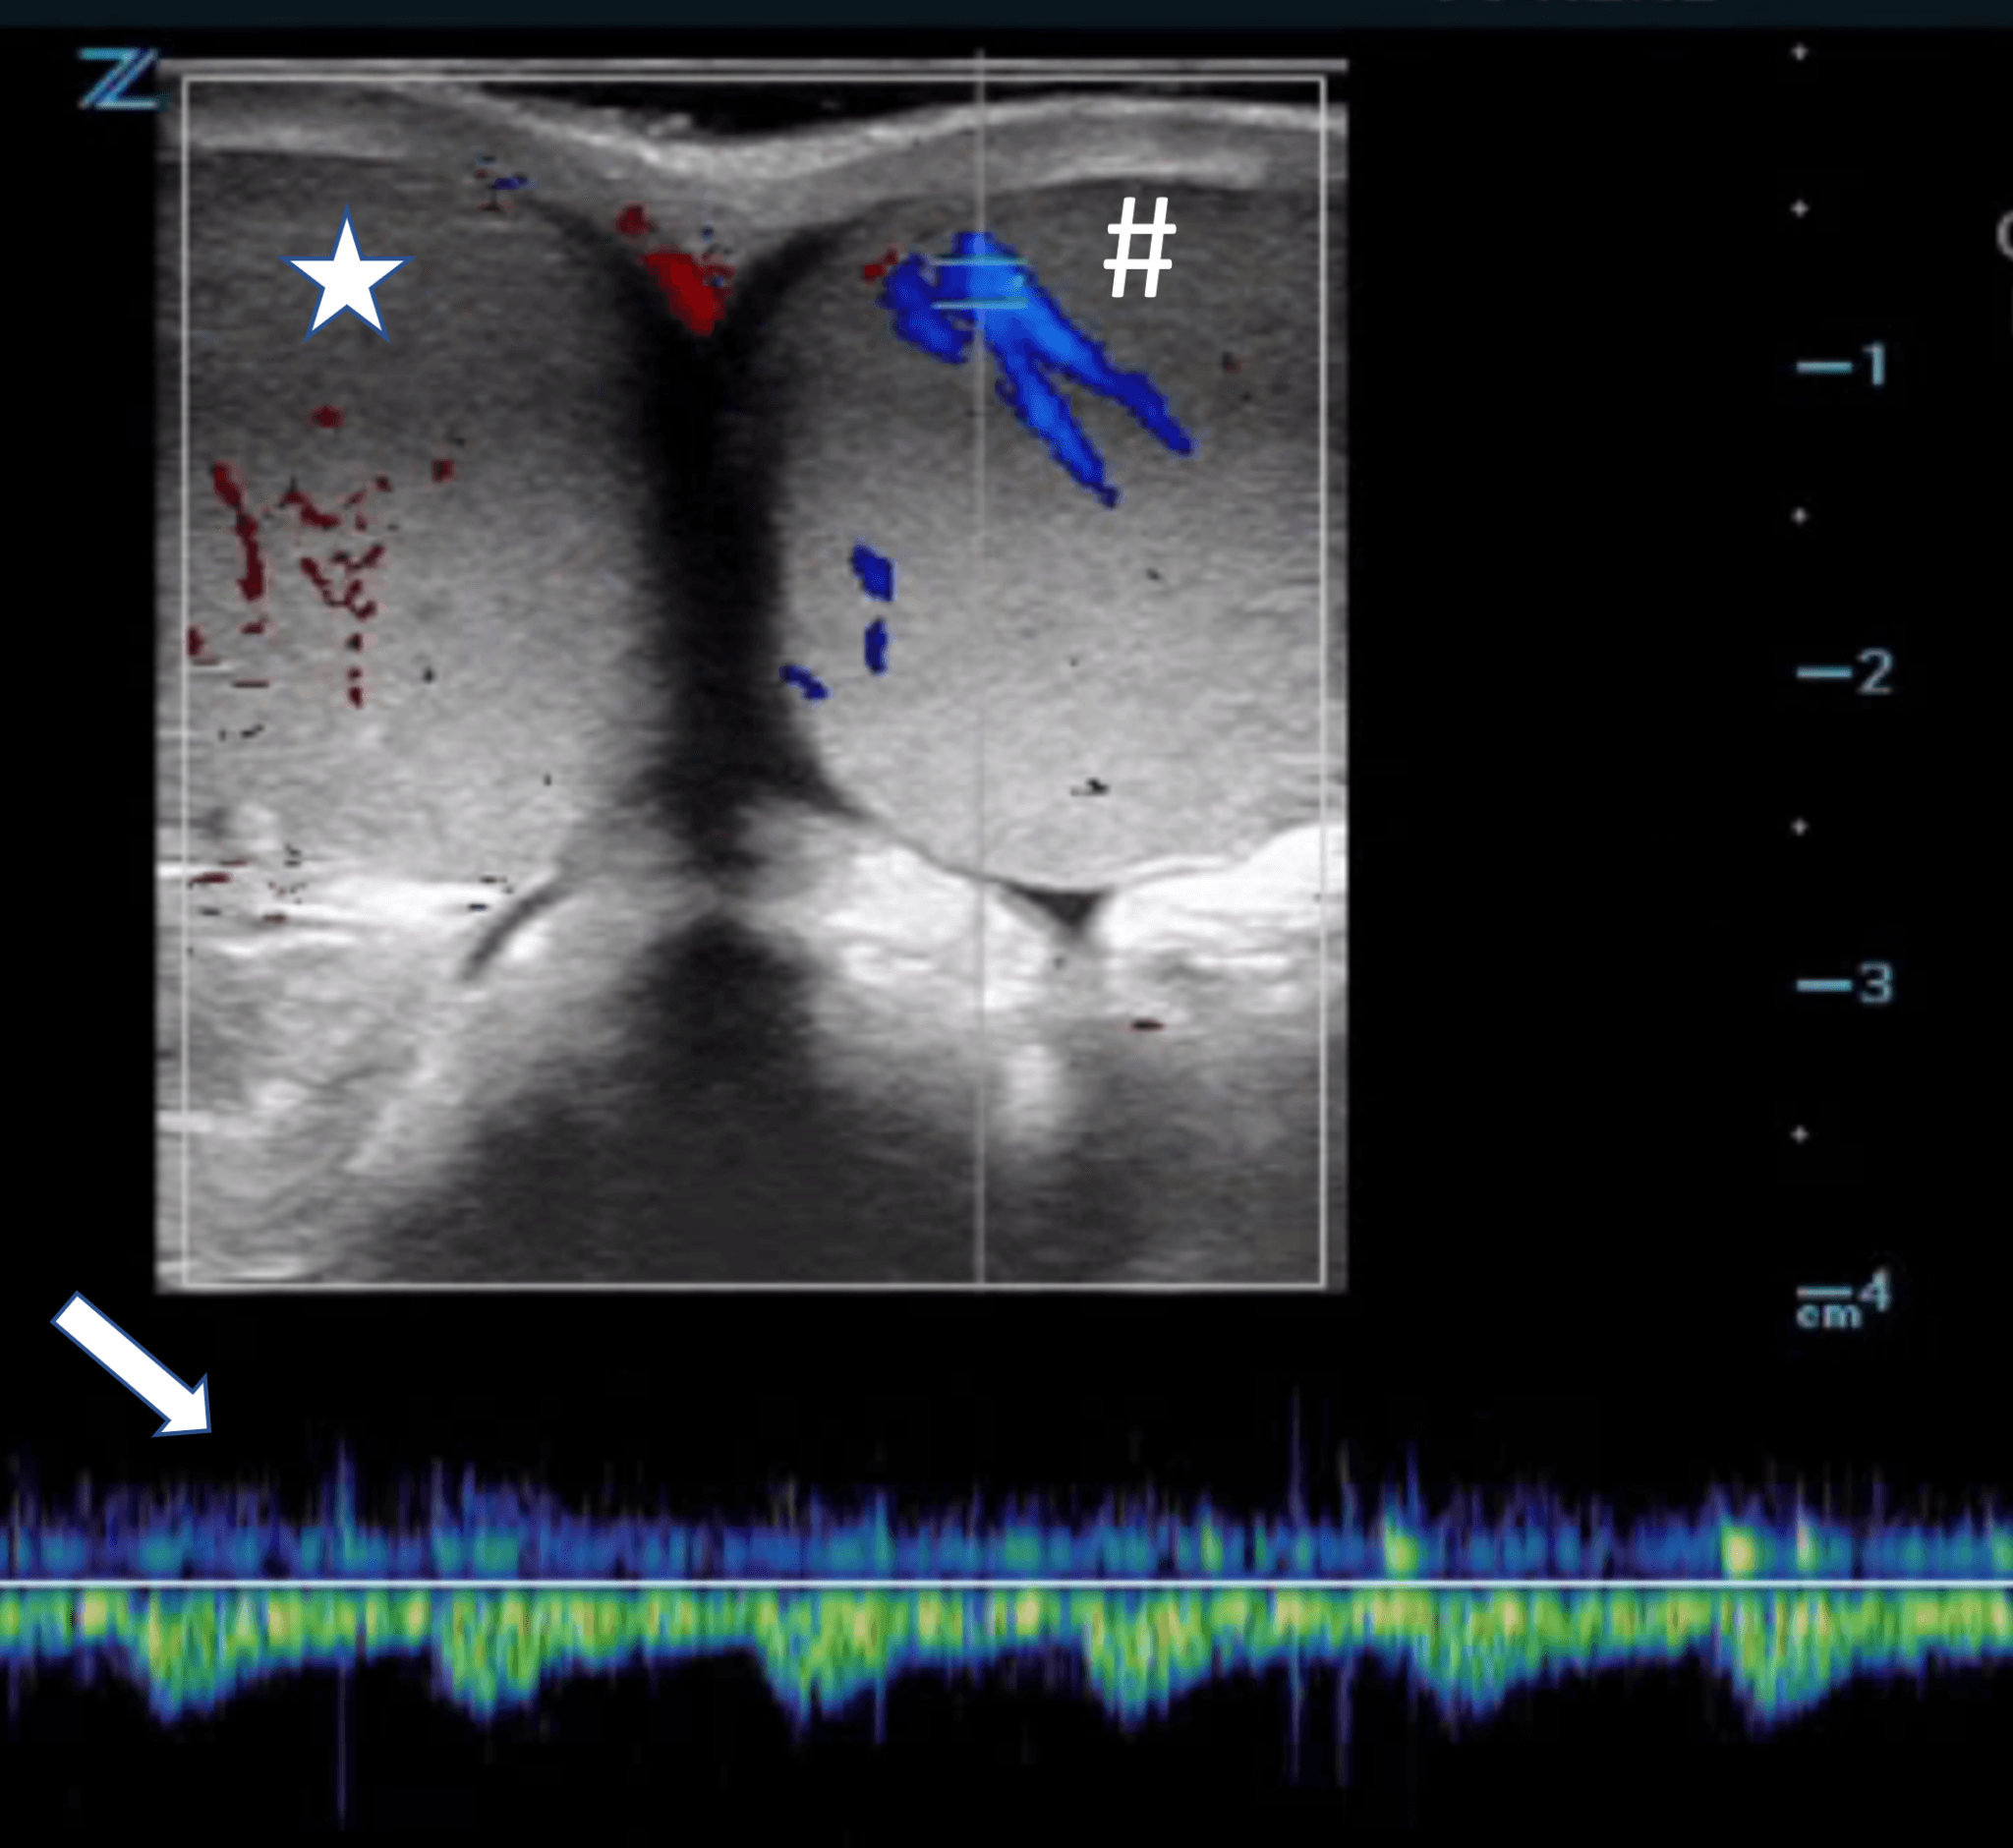

Scrotal Ultrasound Normal Vs Abnormal Image Appearances Scrotum Testicular Torsion Urgent Care an urgent ultrasound would be arranged if required. testicular torsion background testicular torsion is a twisting of the testicle along the longitudinal axis of the. testicular torsion causes your testicle to twist and cuts off its blood supply. the diagnosis of acute scrotal pain can be difficult, with common causes of acute scrotal pain in 7. Testicular Torsion Urgent Care.

Ultrasound of Testicular Torsion RECAPEM Testicular Torsion Urgent Care an urgent ultrasound would be arranged if required. It causes severe pain and requires emergency care. Prompt treatment can prevent severe damage or loss of your testicle if. seek emergency care for sudden or severe testicle pain. an urgent ultrasound would be arranged if required. testicular torsion causes your testicle to twist and cuts off its. Testicular Torsion Urgent Care.

Testicular torsion color Doppler ultrasonography. An echopenic right Testicular Torsion Urgent Care It causes severe pain and requires emergency care. testicular torsion background testicular torsion is a twisting of the testicle along the longitudinal axis of the. clinical practice guideline for management of testicular torsion in urgent care (uc) *exclusion criteria: an urgent ultrasound would be arranged if required. In turn, this causes the spermatic cord from which it.. Testicular Torsion Urgent Care.